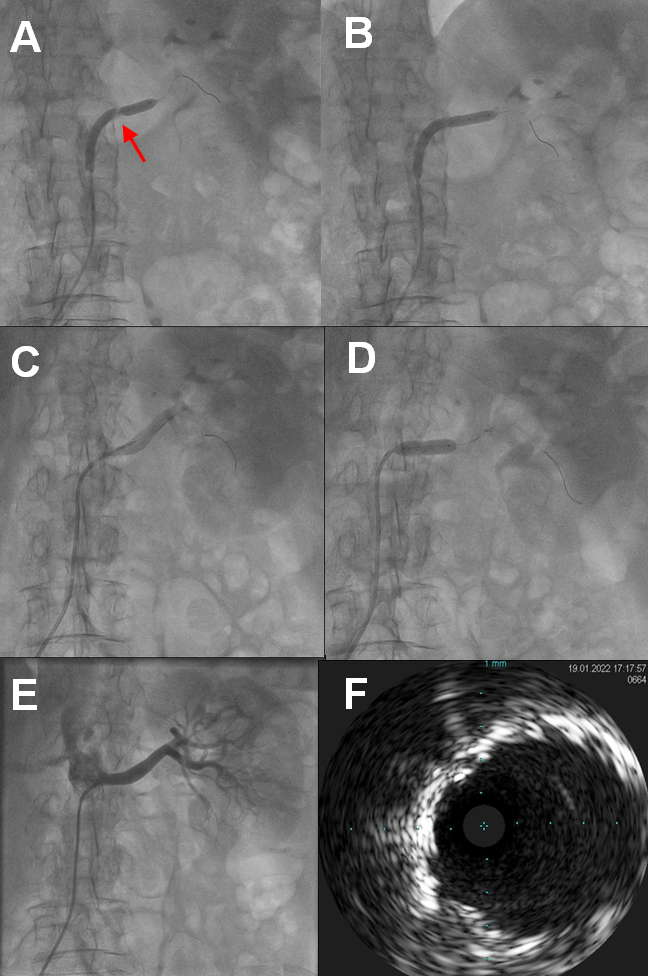

Renal artery angiogram through the right femoral artery demonstrated a critical severe (> 90%) ostioproximal left RAS (Figure 2A; Video 1) and a non-critical right RAS. Left renal artery was engaged with a 6-French renal double curve guide catheter, and a 300-mm 0.014-inch Regalia XS wire (Asahi) was advanced into a renal artery branch. Intravascular ultrasound (IVUS) showed a 6.0- to 6.2-mm reference diameter with metastenotic dilation up to approximately 7.5 mm, and severe superficial and deep calcification at the site of the RAS (Figure 2B). A Shockwave 5 x 60-mm intravascular lithotripsy (IVL) balloon was advanced across the lesion, and the guide catheter was withdrawn into the abdominal aorta. A total of 180 pulses was administered (6 cycles of 30 pulses each), as the initial cycles did not allow adequate expansion of the IVL balloon (Figure 3A, B; Videos 2 & 3). The lesion was then dilated with a 5 x 20-mm non-compliant balloon, and finally a 6 x 18-mm Express stent (Boston Scientific) was deployed with excellent angiographic result, which was confirmed with IVUS (Figure 3C-F; Videos 4-7).